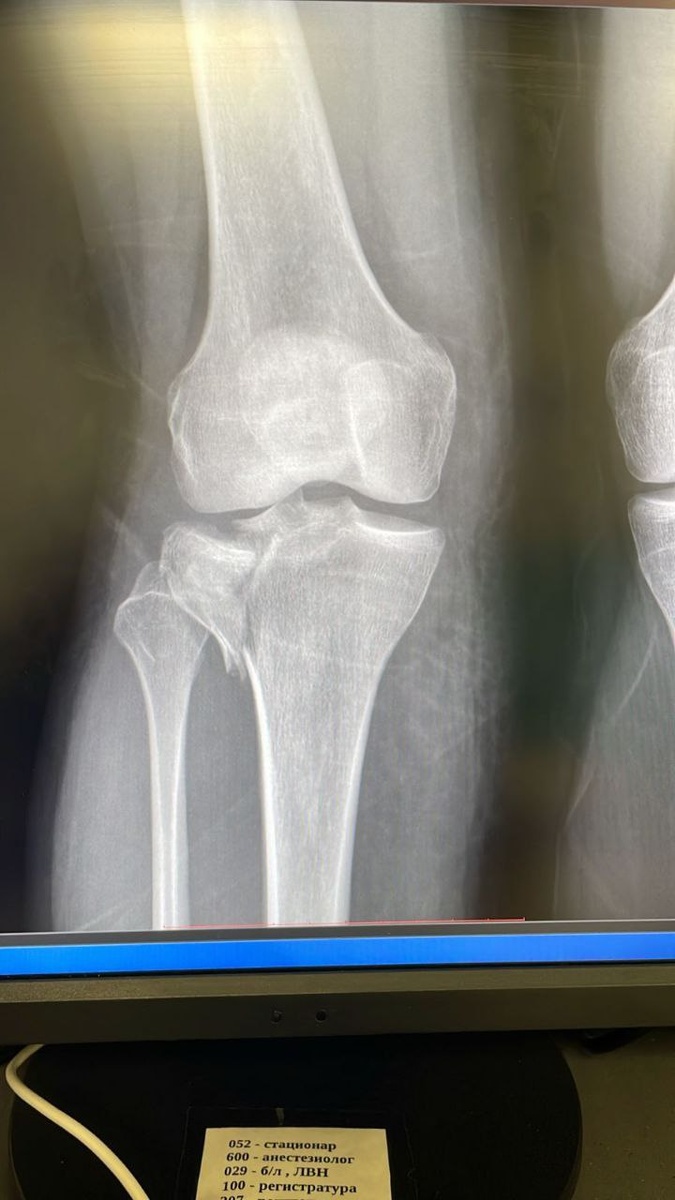

Пациентка подвернула ногу. Обратилась по месту жительства в травмпункт в области. Ее осмотрели, сказали, что перелома не видят, но, спасибо травматологам, заподозрив разрыв связок, на всякий случай, наложили гипсовую лонгету, и отпустили домой. Пациентка обратилась к нам самостоятельно. При обследовании был выявлен оскольчатый внутрисуставной импрессионный перелом наружного мыщелка большерцовой кости со смещением отломков. Суставная поверхность, если заметите на снимках, разлетелась как стекло, на мелкие кусочки. Пациентку быстро обследовали и подготовили к оперирации. Была проведена артроскопия коленного сустава, и остеосинтез пластиной по контролем артроскопии. Пациентке повезло! К счастью, она вовремя обратилась. Чем позже в таких случаях, тем сложнее исправить ошибки. А при первичных снимках возможно не увидеть перелома, так как все еще свежее, и линия перелома может не проявиться, если нет смещения.